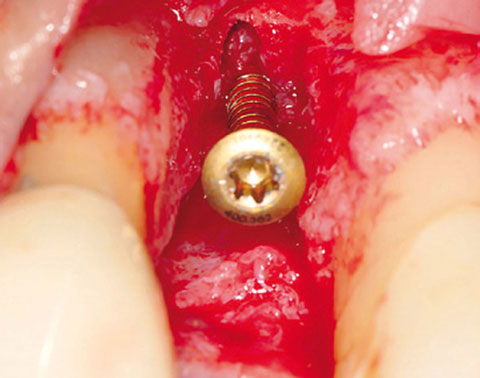

Ein lokaler dreidimensionaler Defekt würde normalerweise mit technikempfindlichen Knochenblöcken behandelt werden.

Durch die Verwendung einer OSSIX® Plus-Membran mit einer Titanschraube als stützender „Zeltstange“ (tent-pole) konnte Randelzhofer zeigen, dass sich derartige Defekte auch durch die Kombination mit partikulärem Knochenersatzmaterial regenerieren lassen.6

Behandlung eines ausgeprägten Knochendefekts in der ästhetischen Zone mit OSSIX® Plus-Membran auf einer Titanschraube als „Zeltstange“ und partikulärem Knochenersatzmaterial (li und Mi). Nach 5 Monaten war der Defekt optimal regeneriert, sowohl in vertikaler als auch in horizontaler Dimension (re).